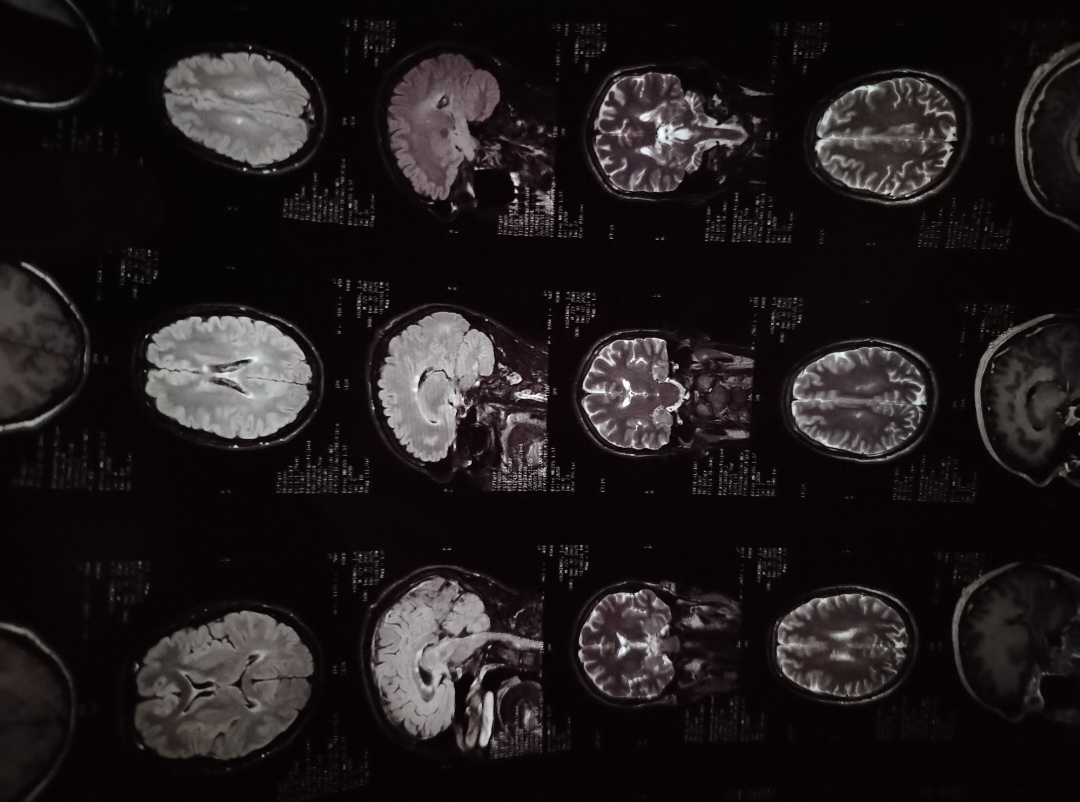

Анончики, в свои 30 заработал остео ШОП.

По-хорошему МРТ головного мозга сделать бы.

Делал уже с контрастом, дал врачу посмотреть, сказал ничего особенного.